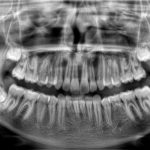

S novim Scan Ceph modulom i drugim inovacijama, najinteligentniji CBCT sustav na svijetu sada je još pametniji i svestraniji nego ikad. Sustav redefinira kvalitetu i upotrebljivost, što ga čini savršenim sustavom snimanja za stomatologe i specijaliste koji žele novu razinu preciznosti.

Kristalno jasne slike s ograničenim artefaktima i šumom

Najširi raspon veličina volumena s do 14 vidnih polja